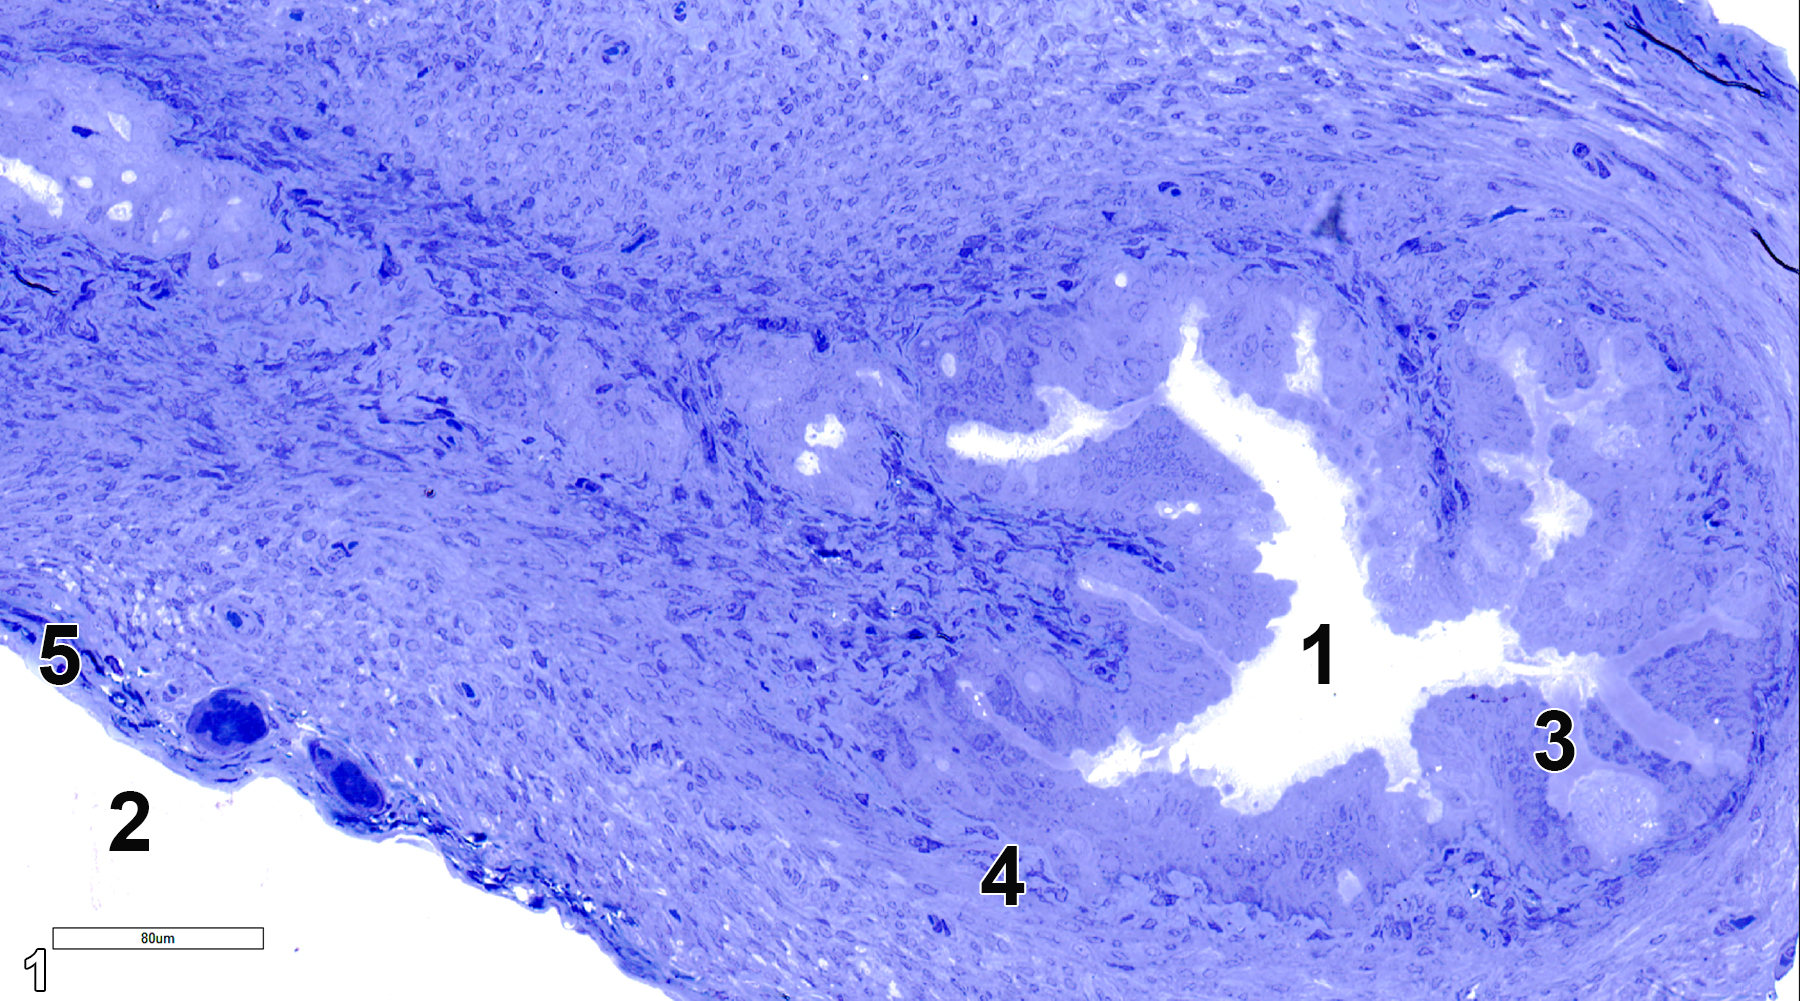

The two oviducts start with the infundibulum, which has a wide opening toward the peritoneal cavity with fimbriae. This is connected to the ampulla, which narrows toward the uterus to form the isthmus attached to the uterus. The surface of the oviduct is lined with a columnar epithelium that contains ciliated cells (approximately 50% of the cell population) and secretory cells that produce mucoprotein nutritive materials. Below the epithelial layer is a muscularis layer that consists of smooth muscle cells and connective tissue. The serosa of the oviduct is covered with a layer of squamous epithelial cells and connective tissue with fibroblasts.